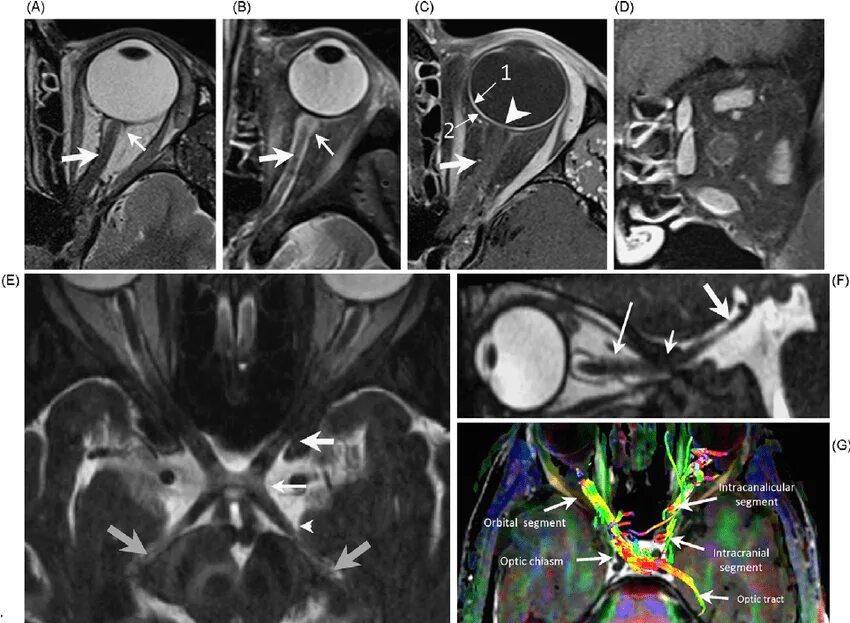

Субарахноидальное пространство зрительных нервов